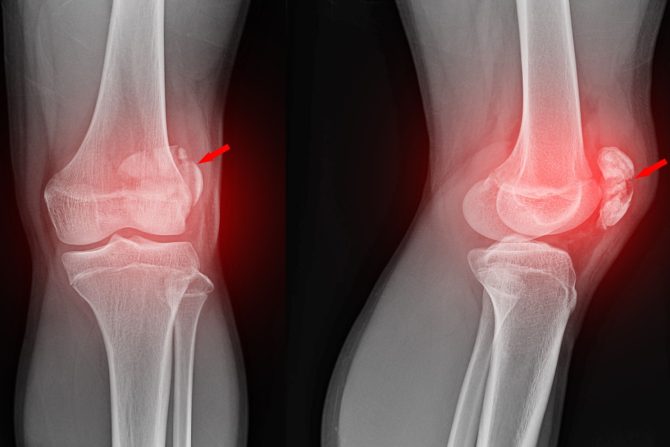

• Dislokacija patele

• Patelarna nestabilnost

• Prelomi patele

• Dislokacija patele naspram subluksacije patele.

Subluksacija je delimična dislokacija. To znači da je kost nestabilna u zglobu i da je možda malo skrenula sa svog mesta, ali nije iskočila do kraja. Kada imate subluksaciju patele, kolenska kapica i dalje stoji u svom žlebu i još uvek možete da hodate. Možda ćete se osećati nelagodno ili nesigurno, a možda će se čuti pucketanje dok se patela pomera. Povrede ili previše labav zglob mogu izazvati subluksaciju patele. Ako imate nove simptome u kolenima ili imate problema sa hodanjem ili kretanjem, zakažite lekraski pregled.